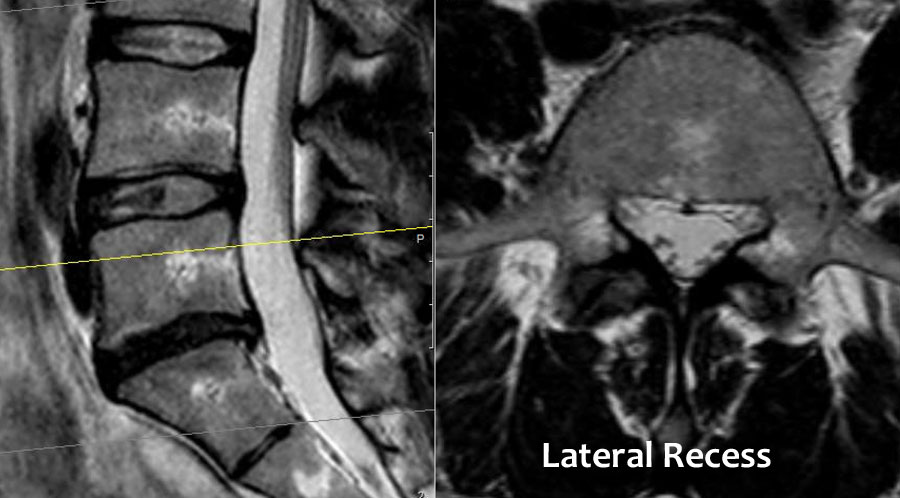

Chủ yếu do thoát vị đĩa đệm và ít thường gặp hơn do hẹp ống sống. - Mức độ ngách bên.

Đây là vùng nằm phía dưới đĩa đệm, nơi rễ thần kinh đi theo hướng bên hơn về phía lỗ liên hợp.

Hẹp ngách bên được gây ra bởi thoái hóa khớp mỏm khớp, thường kết hợp với phì đại dây chằng vàng và phồng đĩa đệm. - Lỗ liên hợp.

Cuộn qua các hình ảnh để quan sát đường đi của các rễ thần kinh tại mức độ đĩa đệm, ngách bên, lỗ liên hợp và ngoài lỗ liên hợp.

Tại mỗi mức độ có thể thấy các bệnh lý đặc trưng, nhưng có sự chồng lấp đáng kể.

Ở bệnh nhân thoái hóa khớp mỏm khớp, các gai xương có thể phát triển vào trong và làm hẹp ngách bên, hoặc phát triển lên trên và làm hẹp lỗ liên hợp.

Khi thoái hóa khớp mỏm khớp nặng xảy ra hai bên, có thể gây hẹp ống sống và chèn ép tất cả các rễ thần kinh tại tầng đó.